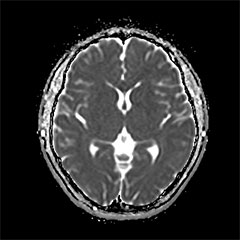

MRI

脳卒中、脳腫瘍、脳萎縮、白室病変、脳室拡大

日本脳ドック学会の推奨する検査内容となります。 頭部MRI検査(T1WI, T2WI, FLAIR, T2*)、頭部MRA検査、頚動脈MRA検査、血液検査、尿検査、心電図検査を行います。